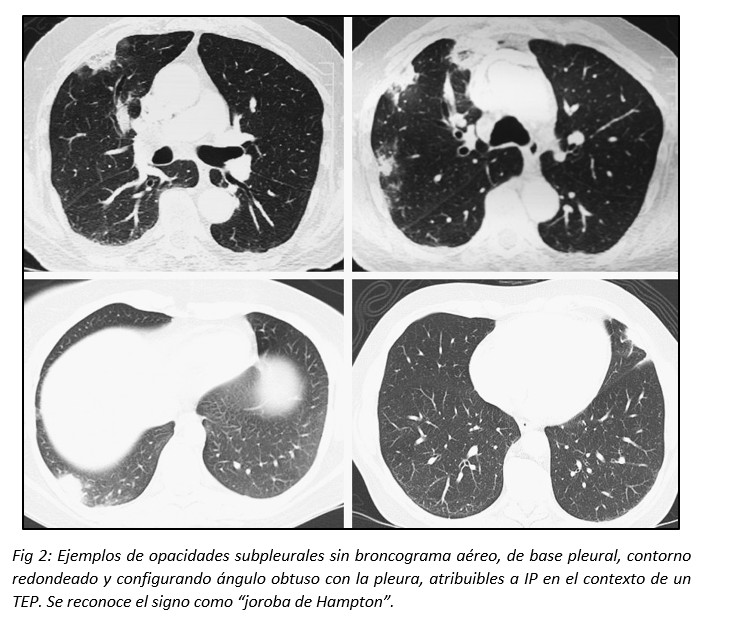

La opacidad puede presentarse sin broncograma aéreo y adoptar una forma redondeada (signo tomográfico conocido como “joroba de Hampton”).1,2 Es habitual que los infartos pulmonares sean confundidos con una NAC, enfermedad granulomatosa o neoplásica debido a la creencia de que el IP debe tener indefectiblemente morfología triangular con su ápex señalando el hilio pulmonar. Hampton y Castleman, y posteriormente Fleischner, describieron que este concepto es erróneo, debido a que el sector apical del área pulmonar afectada por la isquemia tromboembólica suele verse respetada por el infarto, al resultar suficiente el flujo sanguíneo colateral.11,12,13 (Fig 2)